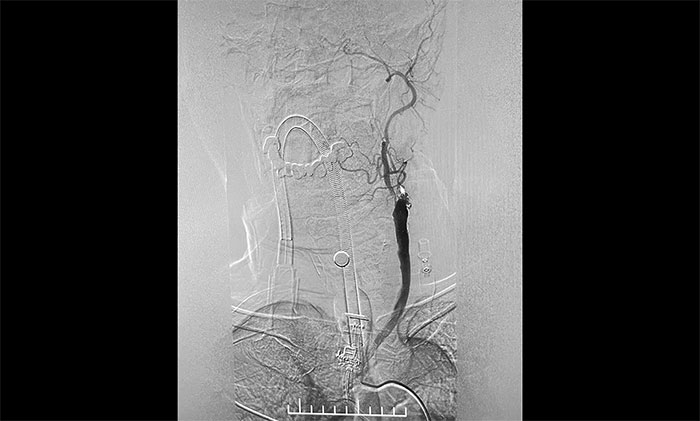

腦血管造影顯示,左頸總動(dòng)脈起始段、下段中度狹窄,左頸外動(dòng)脈起始段重度狹窄,左頸內(nèi)動(dòng)脈起始段閉塞,遠(yuǎn)端頸內(nèi)動(dòng)脈緩慢顯影至眼動(dòng)脈;左椎動(dòng)脈、左大腦后動(dòng)脈、基底動(dòng)脈顯影,左椎V4段經(jīng)側(cè)枝向左側(cè)枕動(dòng)脈代償供血至左頸外動(dòng)脈;右頸內(nèi)動(dòng)脈起始段輕度狹窄。

▲ DSA確診左側(cè)頸內(nèi)動(dòng)脈閉塞